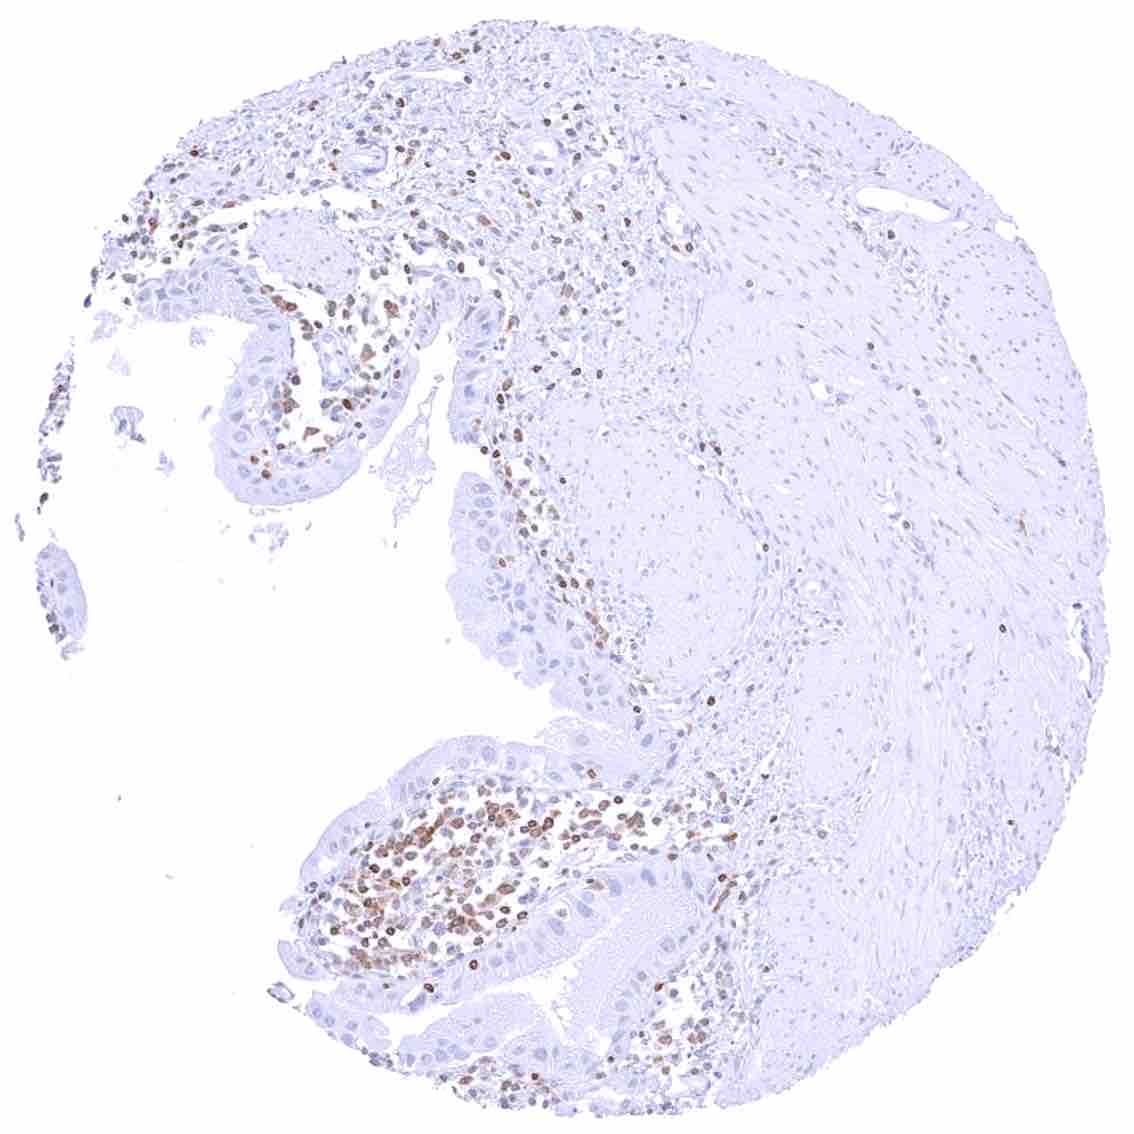

Tonsil –Strong bcl-2 positivity of large fraction of lymphocytic cells in the interfollicular area & around germinal centres. Cells in germinal centres are largely bcl-2 negative. Squamous epithelium with weak bcl-2 staining of the basal cell layer

Tonsil, surface epithelium